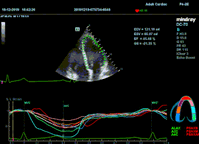

Всё изменилось с появлением технологии Speckle-tracking. Ультразвуковые приборы компании Mindray DC 8, 70, 80, Resona 6,7 оснащены данной функцией. Для использования необходим ЭКГ-канал. В чем же смысл данного технологического новшества? Прибор использует видео петли сечений миокарда, разбивает миокард на точки со стабильной визуализацией – speckle, и затем производит слежение каждой точки в течении нескольких сердечных циклов. Изменение пространства между точками дает нам представление о возможностях деформации миокарда, как продольной – Longitudinal Strain, так и деформации скручивания – торсии и Radial Strain.

На сегодняшний день в мировой клинической практике используется продольный Strain. Методика позволяет выявить нарушения в работе миокарда в каждом отдельном сегменте в среднем до 5 лет раньше клинического манифеста. Так же есть возможность оценки и диастолической функции, с гораздо более высокой чувствительностью чем тканевой допплер. Возможности радиального стрейна изучаются, за этой методикой будущее.

Как работать с данным методом? Для Longitudinal Strain необходимо записать видео петли апикальных сечений в память прибора: 4С, 3С, 2С. Для повышения качества трекинга рекомендуется производить запись на выдохе пациента. Затем произвести разметку по линии эпикарда, перикарда и центра миокарда. Нажатием кнопки «начать слежение» активируется программный алгоритм, видео петля оживает вместе с размеченными точками-speckle’ами. При необходимости производится коррекция. После анализа всех трех сечений можно получить данных продольной деформации как в среднем значении, так и по каждому сегменту миокарда левого желудочка. Нормальным показателем считается Longitudinal Strain -20%. Нижней границей -14%.

Видео примеры на приборе Mindray DC 70